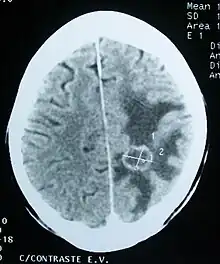

Imaging

CT scan of a brain tumor, with its diameters marked as an X. There is hypoattenuating (dark) peritumoral edema in the surrounding white matter, with a "finger-like" spread.

Medical imaging plays a central role in the diagnosis of brain tumors. Early imaging methods – invasive and sometimes dangerous – such as pneumoencephalography and cerebral angiography have been abandoned in favor of non-invasive, high-resolution techniques, especially magnetic resonance imaging (MRI) and computed tomography (CT) scans,[38] though MRI is typically the reference standard used.[41] Neoplasms will often show as differently colored masses (also referred to as processes) in CT or MRI results.

• Benign brain tumors often show up as hypodense (darker than brain tissue) mass lesions on CT scans. On MRI, they appear either hypodense or isointense (same intensity as brain tissue) on T1-weighted scans, or hyperintense (brighter than brain tissue) on T2-weighted MRI, although the appearance is variable.

• Contrast agent uptake, sometimes in characteristic patterns, can be demonstrated on either CT or MRI scans in most malignant primary and metastatic brain tumors.

• Pressure areas where the brain tissue has been compressed by a tumor also appear hyperintense on T2-weighted scans and might indicate the presence of a diffuse neoplasm due to an unclear outline. Swelling around the tumor known as peritumoral edema can also show a similar result. This is because these tumors disrupt the normal functioning of the BBB and lead to an increase in its permeability.